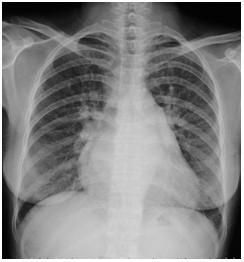

01卷-3.根據(jù)下圖請(qǐng)做出正確診斷(本題滿分2.00分)

A.正常心臟

B.心肌病(普大心)

C.風(fēng)濕性心臟病(梨型心)

D.主動(dòng)脈型心(靴型心)

本題答案:C

【該題針對(duì)“ X線-心臟增大(尖瓣型、主動(dòng)脈型和普大型) ”知識(shí)點(diǎn)進(jìn)行考核】